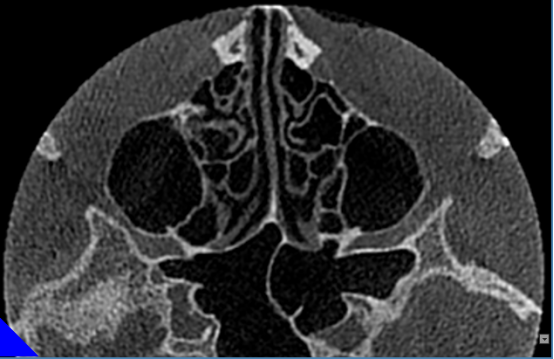

窦部扫描提供窦部综合性判断。